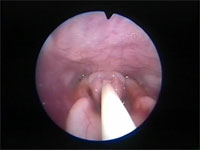

Abb 7 Rima-offen-Plica-zu

Abbidlung 7: Weiter fortschreitender Laryngospasmus gegenüber Abbildung 6.

Abb 6 Laryngeales-Ödem

Abbildung 6: Larynx nur noch halb geöffnet. Die Stimmbänder liegen bereits eng aneinander.

Abb 8 Schlüsselloch-beim-Laryngos

Abbildung 8: Laryngospasmus - nur noch das kleine obere „Schlüsselloch“ der Rima glottidis ist geöffnet.

Selbst bei ausgeprägtem Laryngospasmus bleibt bei der Katze im dorsalen Bereich der Rima glottidis eine winzig kleine Öffnung erhalten. Dieses „Schlüsselloch" kann man bei der Notintubation der Katze (siehe unten) immer mit einem dünnen Mandrin passieren, selbst wenn die Stimmlippen fest aneinander gepresst sind. Für eine funktionelle Atmung reicht die kleine Öffnung jedoch keinesfalls aus.